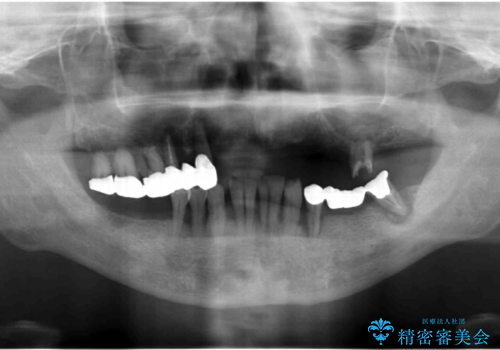

精査したところ、全顎的な重度の歯周病により右下の大臼歯2本(右下76)が欠損していました。

禁煙指導と歯周病治療後、右下の大臼歯2本(右下76)のインプラント治療を行いました。